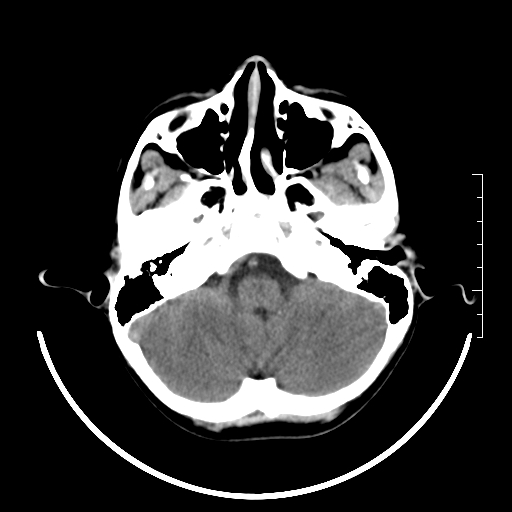

标题: PED3377:m、9y,恶心、呕吐,每月发作2-3次。 [打印本页]

标题: PED3377:m、9y,恶心、呕吐,每月发作2-3次。

颅脑ct轴位平扫颅内未见明确异常。

右侧基底节区见钙化灶

右侧壳核多枚点状钙化灶。去请结合临床。

头颅ct平扫未见异常

颅脑ct平扫未见异常。

桥前池是不是有点大?